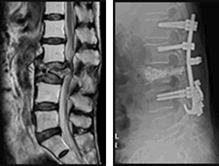

66歳女性:多発腰椎圧迫骨折

腰痛++で治療を継続しないと日常生活が困難です

BKP手術

骨セメント注入療法

左図:第3腰椎圧迫骨折

右図:脊椎固定術